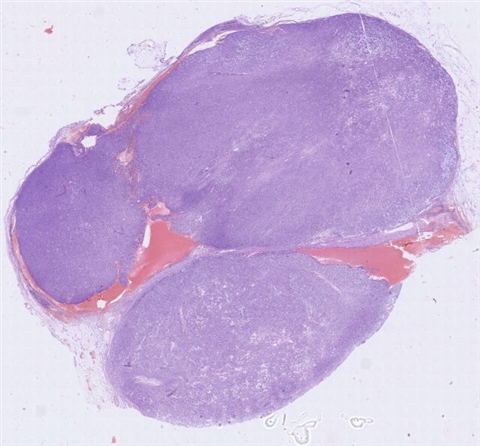

案例1 (6853)

性别:       年龄:77

患者详情: 患者于2018年5月自己扪及颈部肿块,至仁济医院彩超提示右侧多发淋巴结肿大。来我院门诊复查彩超:甲状腺双侧叶占位-考虑良性病变,随访;右侧颈部及右侧锁骨上淋巴结肿大-建议进一步检查。穿刺活检病理提示淋巴组织不典型增生。今患者为求进一步手术治疗就诊于我院,门诊以“颈部肿块”收入院。患者自发病以来,精神食欲可,夜间睡眠可,二便正常,体重无明显减轻。    辅助检查:门诊复查彩超,甲状腺双侧叶占位-考虑良性病变,随访;右侧颈部及右侧锁骨上淋巴结肿大-建议进一步检查。 介入彩超穿刺活检病理提示淋巴组织不典型增生。 体格检查: T: 36.4℃ P: 65次/分 R: 65次/分 BP:130 /75 mmHg

医院: 复旦大学附属中山医院